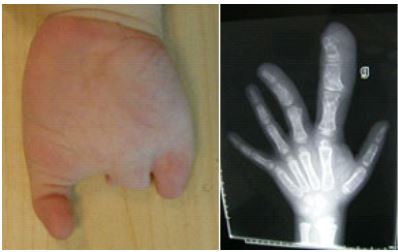

duplication du pouce de type IV de Wassel (images Dr Bigorre, Montpellier)